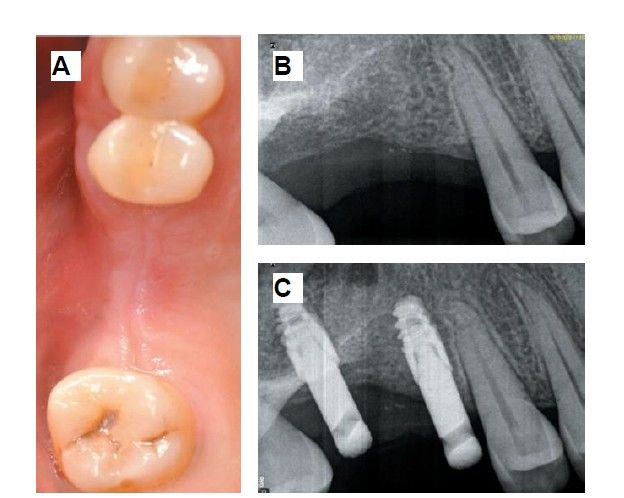

The medical history revealed no relevant medical or surgical antecedents, no known drug allergies, and no harmful habits. Intraoral examination revealed the absence of 1.6 and 1.7, and the presence of 1.8 and 4.8 (Figure 1). Radiographic examination using cone beam computed tomography (CBCT) revealed a residual height of 5.0 mm at 1.6, where an implant could be placed simultaneously, and 2.6 mm in the region of 1.7, making simultaneous implant placement with the lateral approach sinus elevation difficult (Figure 2).

Six months after the maxillary sinus elevation surgery, re-entry was performed for the placement of implants. A 3 x 7mm bone tissue biopsy was obtained using a trephine, and histomorphometric analysis was requested, revealing 30.56% vital bone (Figure 7). After the biopsy sample was taken, two bone level Naturactis implants from ETK® (ETK Implants S.L, Sant Boi de Llobregat, Spain) were placed with an insertion torque of 35 Ncm, and their correct positioning was confirmed in the immediate postoperative period by means of a periapical radiograph (Figure 8). Six months after the placement of the implants, the patient was able to attend for the second stage to place healing abutments. A verification CBCT was performed to assess the final bone height, revealing an increase of 4.2 mm in the region of 1.6 and 6.1 mm in the region of 1.7 (Figure 9).

Fifteen days after the second stage, impressions were taken for the fabrication of two splinted cement-screw-retained crowns on titanium bases, with the fit verified by a parallelised periapical radiograph (Figure 10). Six months after placement of the restoration, a clinical and radiographic review was conducted, noting the favourable condition of the soft tissues (Figure 11).